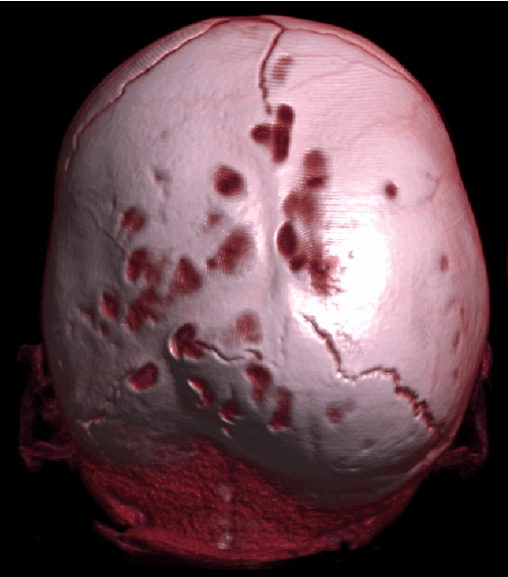

Рис. №2 а) – вариант нормы

б) – деформация черепа вызванная синостозом (слиянием) лямбдовидного шва слева, указателем показаны множественные пальцевые вдавления (истончение костной ткани, вплоть до появление «дыр»).